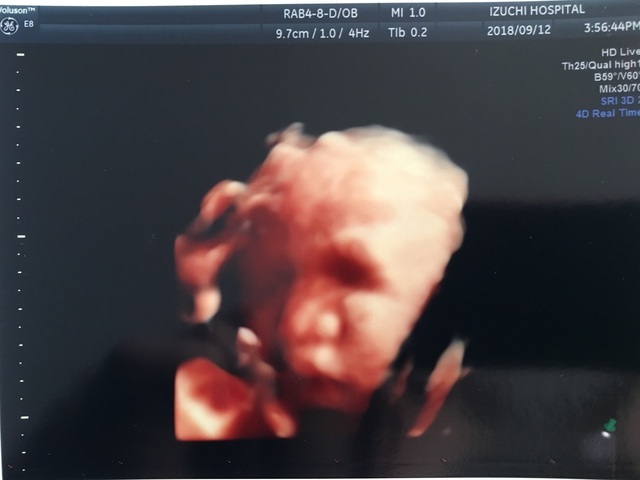

23週5日(23w5d・女の子)|misakikura さん(33歳)

エコー写真撮影時のエピソード:

まさかの足での敬礼。産婦人科の先生も、足で敬礼してる子はなかなかいないねって笑ってました。もっと前に撮ったエコーではここまで顔立ちハッキリしてなくわからなかったですが、、この時のエコーは鼻と口元が主人にそっくりでびっくり。主人に「似てるね」って話したら、「そうかなぁ?」って照れながら喜んでました。